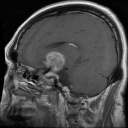

MRI Data Augmentation Using GANs

Jan 2024Developed a Generative Adversarial Network to address the issue of data scarcity in medical-based data science.